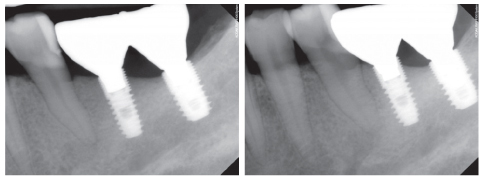

Figure 4

Location of mental foramens (dotted line) and periapical radiolucency (arrow).

Figure 4 Location of mental foramens (dotted line) and periapical radiolucency (arrow).